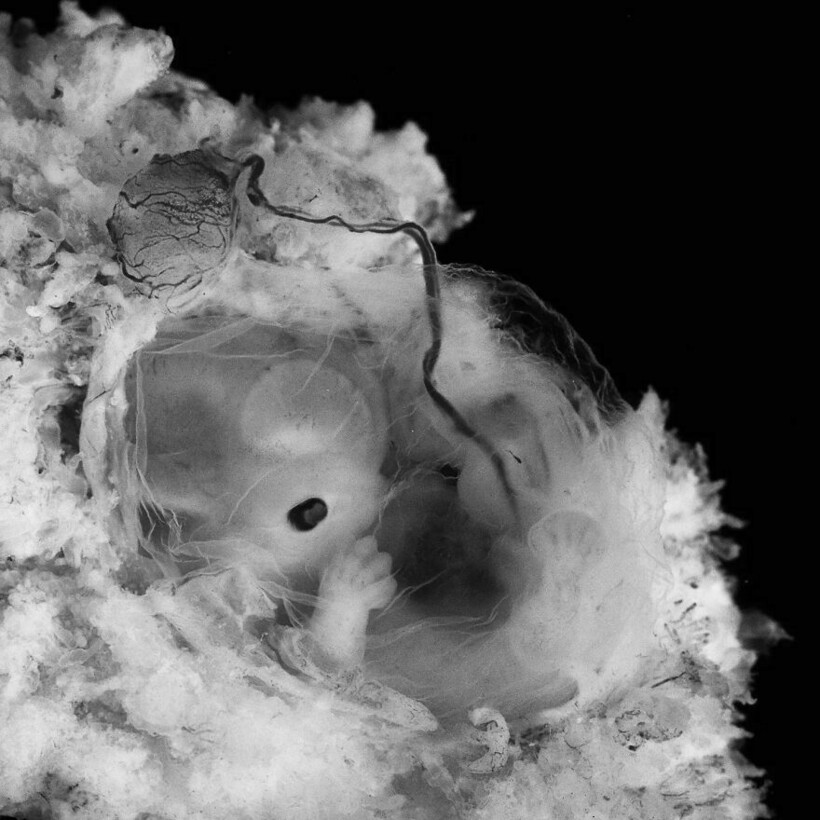

Леннарт Нильссон стал настоящей легендой фотографии, ведь он сделал то, чего не удавалось никому: показал миру, как развивается ребенок в утробе матери. Его проект «Ребенок родился» был создан в 1960-х годах, и он представляет собой детальные снимки эмбрионов на разных стадиях развития. Фотографии стали сенсационными, впервые они появились в журнале LIFE, и одна из них украсила обложку. На протяжении многих лет эти снимки публиковали в разных журналах.

Фотограф снимал детей в утробе матерей во время медицинских процедур

Он присутствовал на амниоцентезе и лапароскопии

Нильссон не скрывал, что снимал и эмбрионы после выкидышей и абортов

Снимки стали сенсацией, их много раз перепечатывали, они и сегодня вызывают отклик у зрителей

Его фото позволили заглянуть в чудо рождения, они стали источником знаний и вдохновения